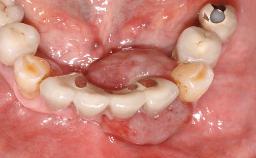

Surgical treatment of a 68-year-old female patient with a distal extension situation in the left mandible. As the CBCT analysis reveals, the bone crest anatomy in the area is not ideal and necessitates an augmentation procedure to achieve a good long-term prognosis for the planned implants and their prostheses.

Case Type Extended Space

Jaw Mandible

Area Posterior

# of Teeth 3

# of Implants 3

Bone Volume Horizontally and vertically sufficient Horizontally deficient Deficient vertically or deficient vertically AND horizontally

Bone Volume Deficient horizontally, allowing simultaneous augumentation